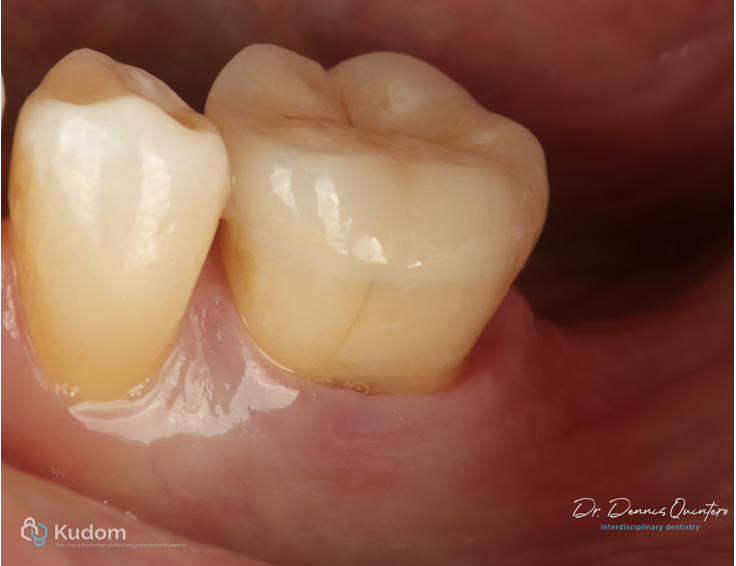

Fig. 4

. Occlusion diagnosis.

. Absence of 3.7.

. Is very important to make the correct restoration to avoid any vertical fracture in the future.